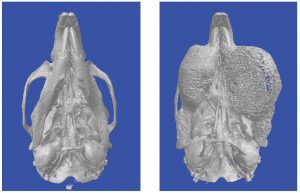

Osteoporose: Neue Teile im großen Puzzle17. November 2017 Diese Mikro-Computertomographie-Aufnahme zeigt Knochenquerschnitte im Vergleich. Normale Wildtyp-Mäuse haben eine ausreichende Zahl an Knochenbälkchen (li.). Bei Mäusen, in denen Men 1 in Osteozyten fehlt, ist die Zahl der Knochenbälkchen stark verringert, sodass Osteoporose entsteht. (Aufnahme: Institut für molekulare Endokrinologie) Das Protein Menin spielt eine Schlüsselrolle bei der Knochenbildung und der Entstehung von Kieferkrebs. Wissenschaftlern der Universität Ulm ist es gelungen, mit Menin und CXCL10 wichtige Faktoren bei der Entstehung von Osteoporose zu entschlüsseln. Diese Erkenntnisse bieten einen Entwicklungsansatz für neue Therapien der Volkskrankheit. Parallel entdeckten die Forscher einen Auslöser eines seltenen Unterkiefertumors. Rund zehn Prozent der Bevölkerung in Deutschland leiden an Osteoporose. Bei sieben Prozent der Frauen über 55 Jahren tritt die Krankheit auf, bei den über 80-jährigen Frauen ist bereits fast jede Fünfte betroffen. Auch Männer erkranken immer häufiger. Die Knochen der Betroffenen verlieren zusehends an Festigkeit, die Gefahr von Brüchen steigt. In der Folge werden gerade sehr alte Menschen oft pflegebedürftig. Bei der Erforschung der Volkskrankheit Osteoporose sind Wissenschaftler des Instituts für molekulare Endokrinologie der Tiere (CME) an der Universität Ulm einen wichtigen Schritt vorangekommen. „Wir haben einen neuen Faktor der Regulation von Knochendichte entdeckt“, sagt Institutsleiter Professor Jan Tuckermann. Im Kern der Forschung stand der sogenannte Tumorsuppressor Menin. Das Fehlen dieses Gens in Osteozyten, den für den Knochenumbau zuständigen Zellen, sorgte in den Knochen von Mäusen für die starke Vermehrung knochenabbauender Zellen (Osteoklasten). Zugleich identifizierten die Ulmer Forscher das Molekül CXCL10, das von den Osteozyten ausgesandt wird. „Wird dieses Molekül ausgeschüttet, gibt es mehr Osteoklasten“, erklärt Tuckermann. „Es gibt zwar noch eine Reihe anderer Faktoren, aber wir haben diesem Puzzlespiel zwei neue, bekannte Faktoren hinzugefügt“, sagt der Molekularbiologe, der das CME seit 2012 leitet. Ein Fernziel könnten neue Ansätze für die Behandlung der Osteoporose sein. „Gängige Therapien blockieren den Knochenabbau“, erläutert Tuckermann. Das sei zunächst gut, weil nicht mehr Knochenmasse verloren gehe. Gleichzeitig leide jedoch die Knochenqualität, weil zum Umbau der Knochen, der bei sich verändernden Anforderungen ans Skelett permanent im Körper abläuft, immer ein Beitrag der abbauenden Osteoklasten gehöre. Nachdem einer der Kommunikationswege zwischen Osteozyten und Osteoklasten aufgedeckt ist, könne der Versuch folgen, die Interaktion dieser Zellen zu dämpfen. „Denkbar wäre, das Molekül CXCL10 mit Antikörpern zu verringern“, so Tuckermann. Zumindest sei für solche Überlegungen ein Ansatzpunkt geschaffen. Diese Mikro-Tomographie-Aufnahmen zeigen Unterseiten von Mausschädeln. Der Unterkiefer der Wildtyp-Maus ist normal ausgebildet (li.). Bei Mäusen ohne Men1 in den Osteoblasten kam es dagegen zu Tumoren auf beiden Seiten des Unterkiefers (r.) (Aufnahme: Institut für molekulare Endokrinologie) Die über sieben Jahre laufenden Forschungen haben noch einen Nebeneffekt erbracht: Der Menin-Verlust in den Osteoblasten von Mäusen führte in einigen Fällen zu Tumorbildung im Unterkiefer. Experten des Kiefertumor-Referenzzentrums in Basel, eines Kooperationspartners des CME, wiesen auf die Ähnlichkeit mit dem am Menschen auftretenden Ossifizierenden Syndrom hin. Diese Tumorerkrankung führt zu starkem Zellwachstum im Unterkiefer und ist noch kaum erforscht. Derzeit kann dieser sehr seltene, gutartige Tumor lediglich durch tiefgreifende und entstellende Eingriffe behandelt werden. Bislang war über die auslösenden Faktoren dieser Tumorerkrankung nur wenig bekannt. Jetzt stellten die Ulmer Forscher erstmals in einem Mausmodell fest, dass Menin einen Hemmer des Zellwachstums steuert das sogenannte p21 — und so das Tumorwachstum unterdrückt. Fehlt Menin, vermindert p21 seine Aktivität und bestimmte Zellen beginnen vermehrt zu wachsen. In einem nächsten Schritt wird das Ulmer Institut mit seinen Kollegen des Deutsch-Österreichisch-Schweizer Arbeitskreises für Tumoren aus dem Kiefer und Gesichtsbereich (DÖSAK) humane Proben des Ossifizierenden Syndroms untersuchen, um die Erkenntnisse aus der Arbeit mit Mäusen zu überprüfen. „Wir hoffen, dadurch therapeutische Ansätze zu finden, die das Entstehen dieser Tumoren verhindern könnten“, so Tuckermann. Bei ihrer Arbeit können die Wissenschaftler Tierversuche nicht immer vermeiden. Jedoch reduzieren die Forscher die Anzahl der Tiere auf ein Mindestmaß, mit dem valide Schlussfolgerungen für die Erklärung menschlicher Krankheitsbilder möglich sind. Finanziell unterstützt wurde das Projekt durch Mittel der Deutschen Forschungsgemeinschaft im Rahmen des Schwerpunktprogramms Immunobone 1468, des Trauma SFBs 1149 und des Trilateralen Konsortiums Tu 220/12-1. Literaturhinweise: Liu P, Lee S, Knoll J et al. Loss of menin in osteoblast lineage affects osteocyte-osteoclast crosstalk causing osteoporosis; Cell Death & Differentiation. 2017 Apr; 24(4):672-682. https://doi.org/10.1038/cdd.2016.165 Lee S, Liu P, Teinturier R et al. Deletion of Menin in craniofacial osteogenic cells in mice elicits development of mandibular ossifying fibroma; Oncogene. 2017 Oct 9, doi:10.1038/onc.2017.364